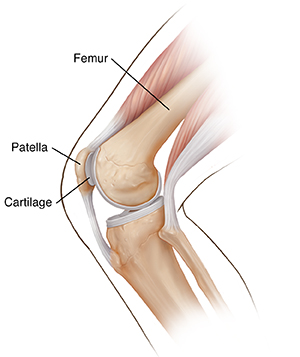

Your kneecap (patella) is a thick, round bone. It covers and protects the front portion of your knee joint. It moves along a groove in your thighbone (femur) as part of the patellofemoral joint. A layer of cartilage surrounds the underside of your kneecap. This layer protects it from grinding against your femur.

When this cartilage softens and breaks down, it can cause knee pain. This is partly because of repetitive stress. The stress irritates the lining of the joint. This causes pain in the underlying bone.